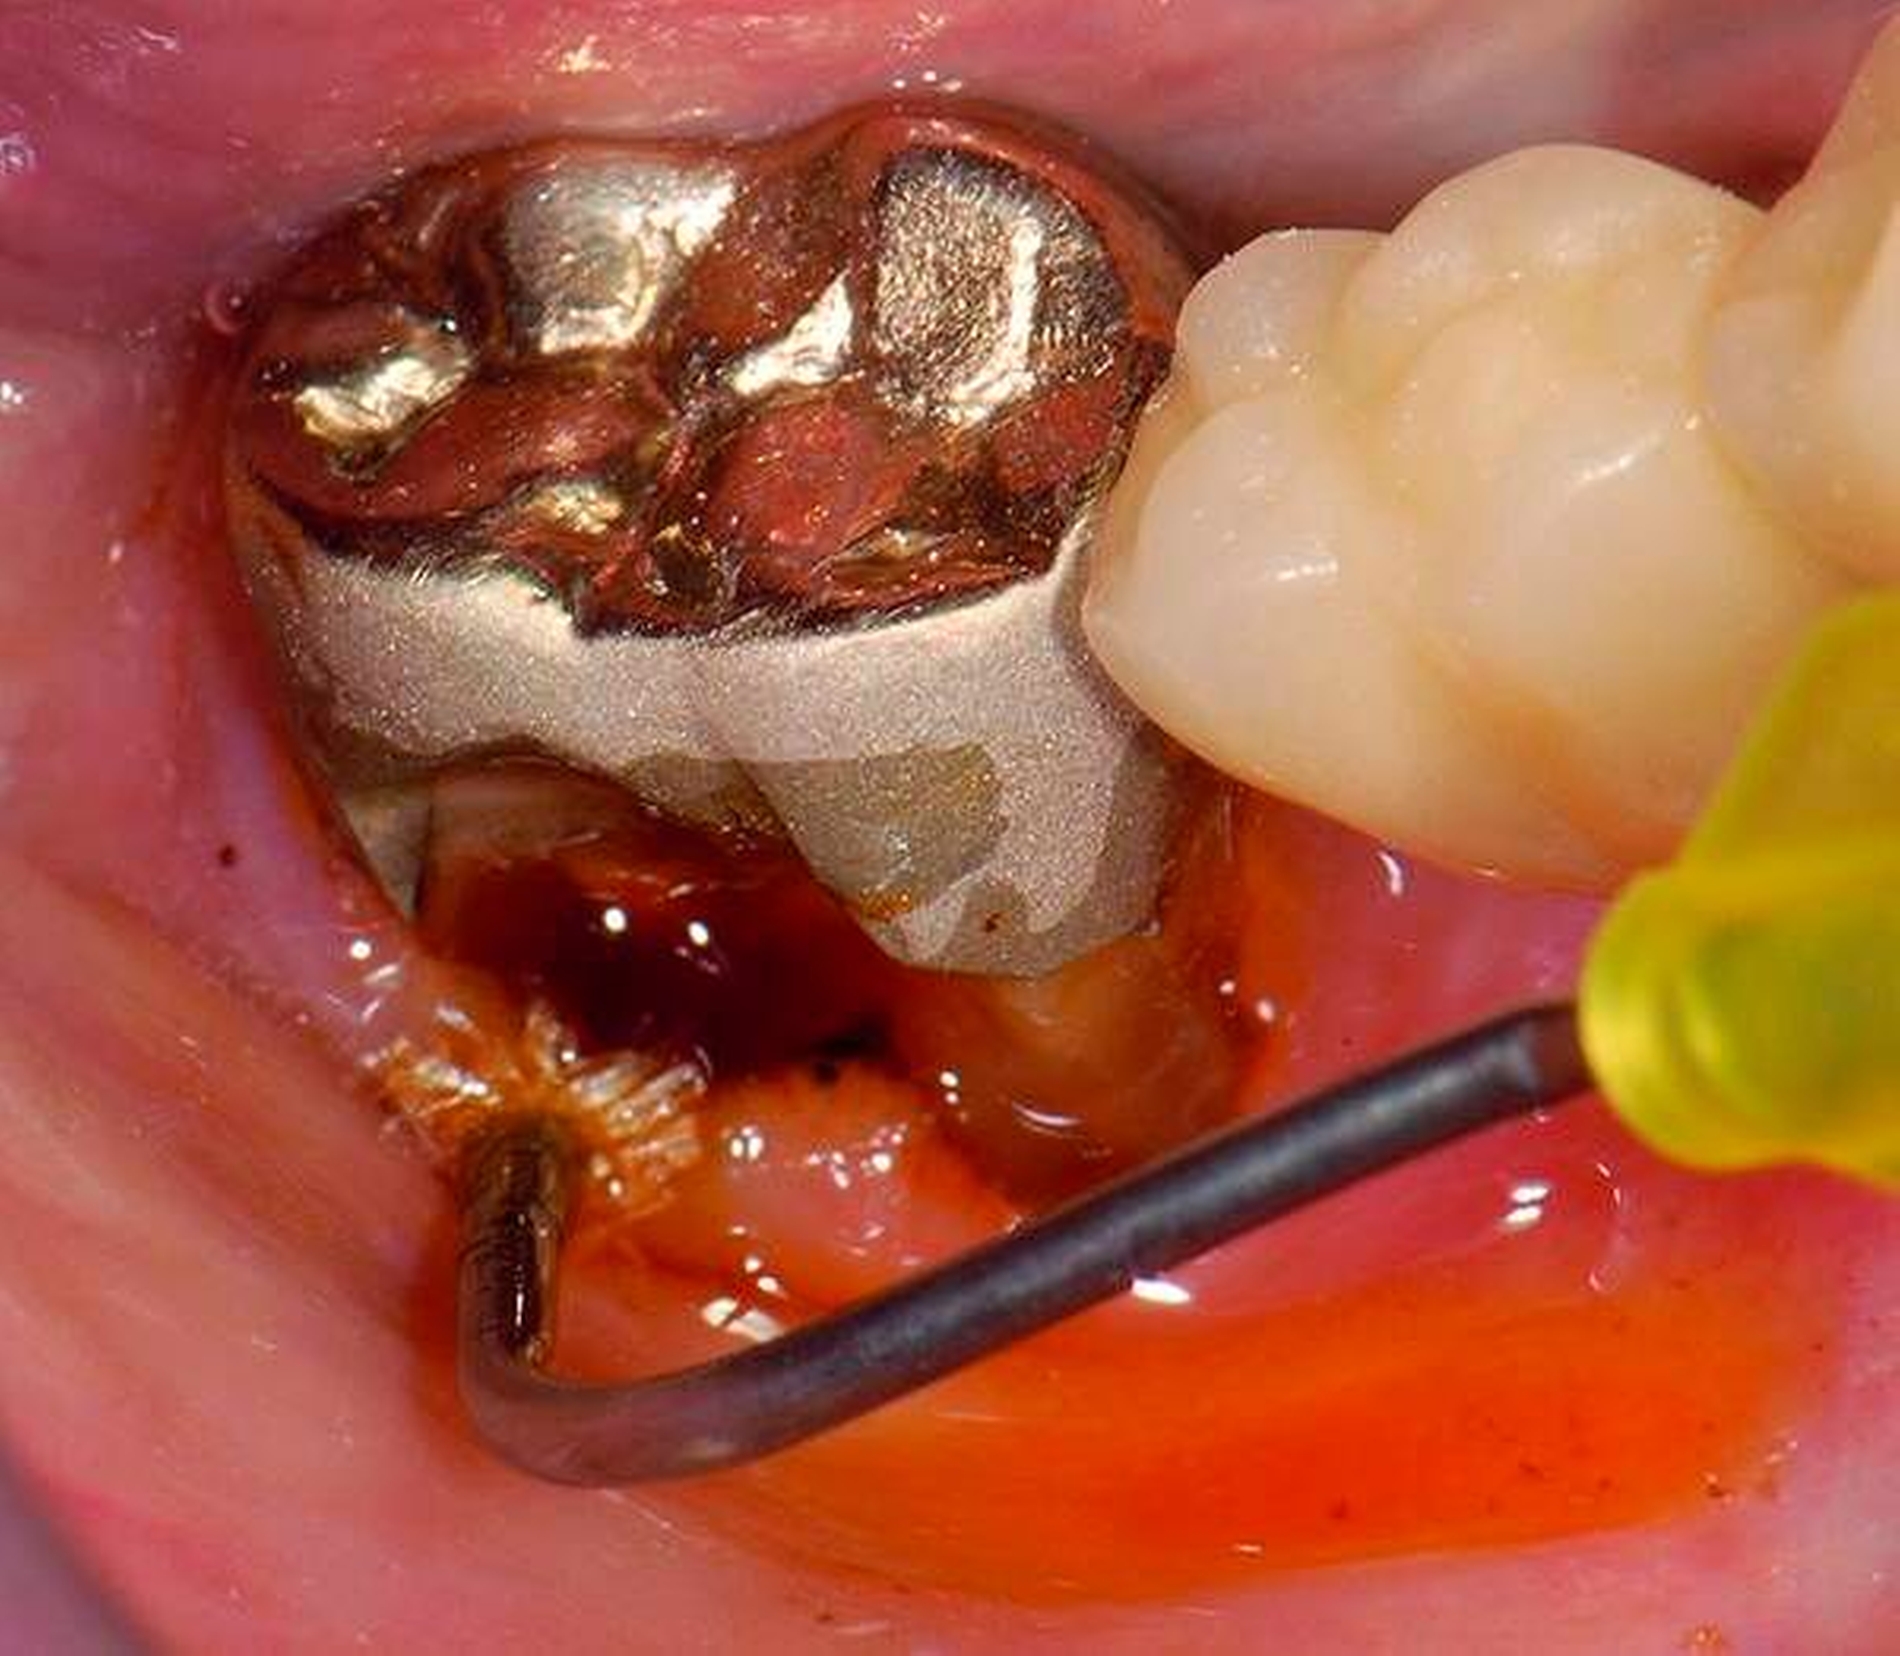

3. Restaurative Versorgungen bei Wurzelkaries

Freiliegende Wurzeloberflächen können im Alter ein locus minoris resistentiae für Karies sein. Im Zusammenspiel ungünstiger Ernährungsgewohnheiten, nachlassender Mundhygiene sowie Änderungen von Speichelquantität und -qualität kommt es zuweilen zu einem präventiv und restaurativ schwer beherrschbaren Auftreten von Wurzelkaries. Gut zugängliche Kariesläsionen können mit einphasig eingebrachtem Komposit (R1-Restaurationen) angegangen werden (Abbildungen 3 bis 5). Bei schwerer zugänglichen Arealen kommt ein zweiphasiges Vorgehen in Betracht (R2-Restaurationen). Das Vorgehen bei der R1- und bei der R2-Technik wurde mehrfach beschrieben [Frese et al., 2014a, b, c, d; Staehle et al., 2014, 2017]. Im Fall von zirkulärer Wurzelkaries sollte frühzeitig eingegriffen werden, da ansonsten die gesamte Zahnkrone frakturieren kann.

Abbildung 3: ausgedehnte Kronen- und Wurzelkaries unter einer Krone am Pfeilerzahn 47 einer seit Jahrzehnten eingegliederten Brücke von 45–47 bei einer 71-jährigen Patientin, die nach einer zerebrovaskulären Erkrankung unter Antikoagulantientherapie steht, vor etwa zwei Jahren hat sie eine Umstellung auf eine fluoridfreie Zahnpaste vorgenommen.